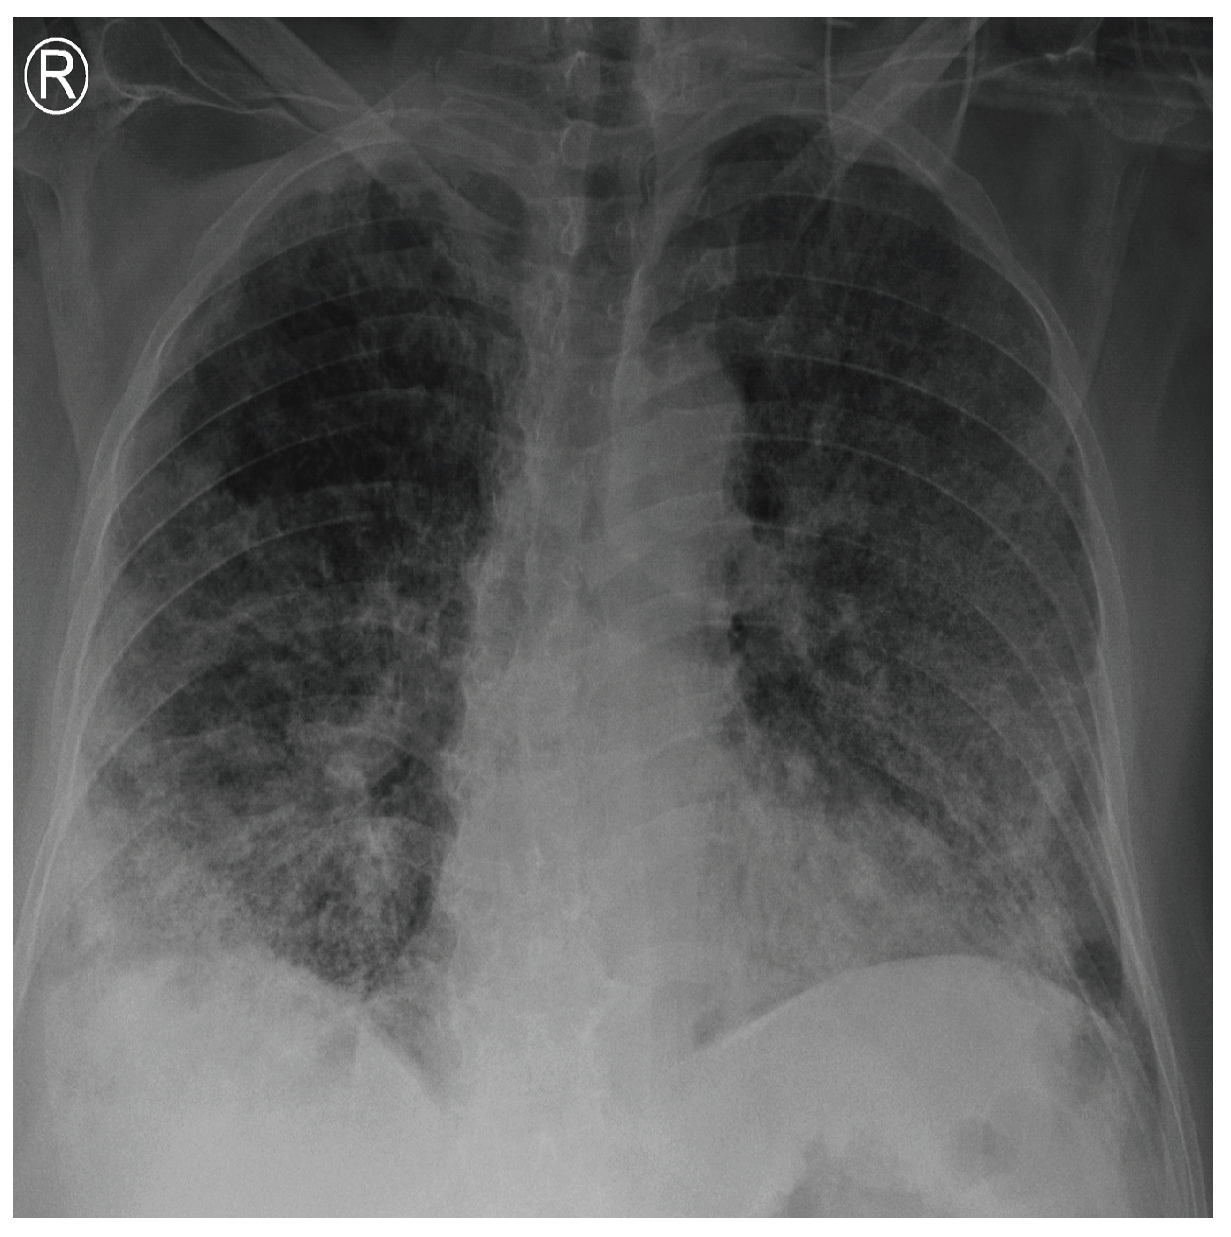

COVID-19 patients who have clinical symptoms are more likely to show abnormal CXR [9]. The main findings of recent studies suggest that these lung images display patchy or diffuse reticular–nodular opacities and consolidation, with basal, peripheral, and bilateral predominance [10]. For example, Figure 1 shows the CXR of a mild case of lung tissue involvement with right infrahilar reticular–nodular opacity. Moreover, Figure 2 shows the CXR of a moderate to severe case of lung tissue involvement. This CXR shows right lower zone lung consolidation and diffuse bilateral airspace reticular–nodular opacities, which are more prominent on peripheral parts of lower zones. Similarly, Figure 3 shows the CXR of a severe case of lung tissue involvement. This is caused by diffuse bilateral airspace reticular–nodular opacities that are more prominent on peripheral parts of the lower zones, and ground glass opacity in both lungs predominant in mid-zones and lower zones. On the other hand, Figure 4 shows an unremarkable CXR with clear lungs and acute costophrenic angles (i.e., normal).

Figure 1.

CXR of COVID-19 subject showing mild lung tissue involvement.